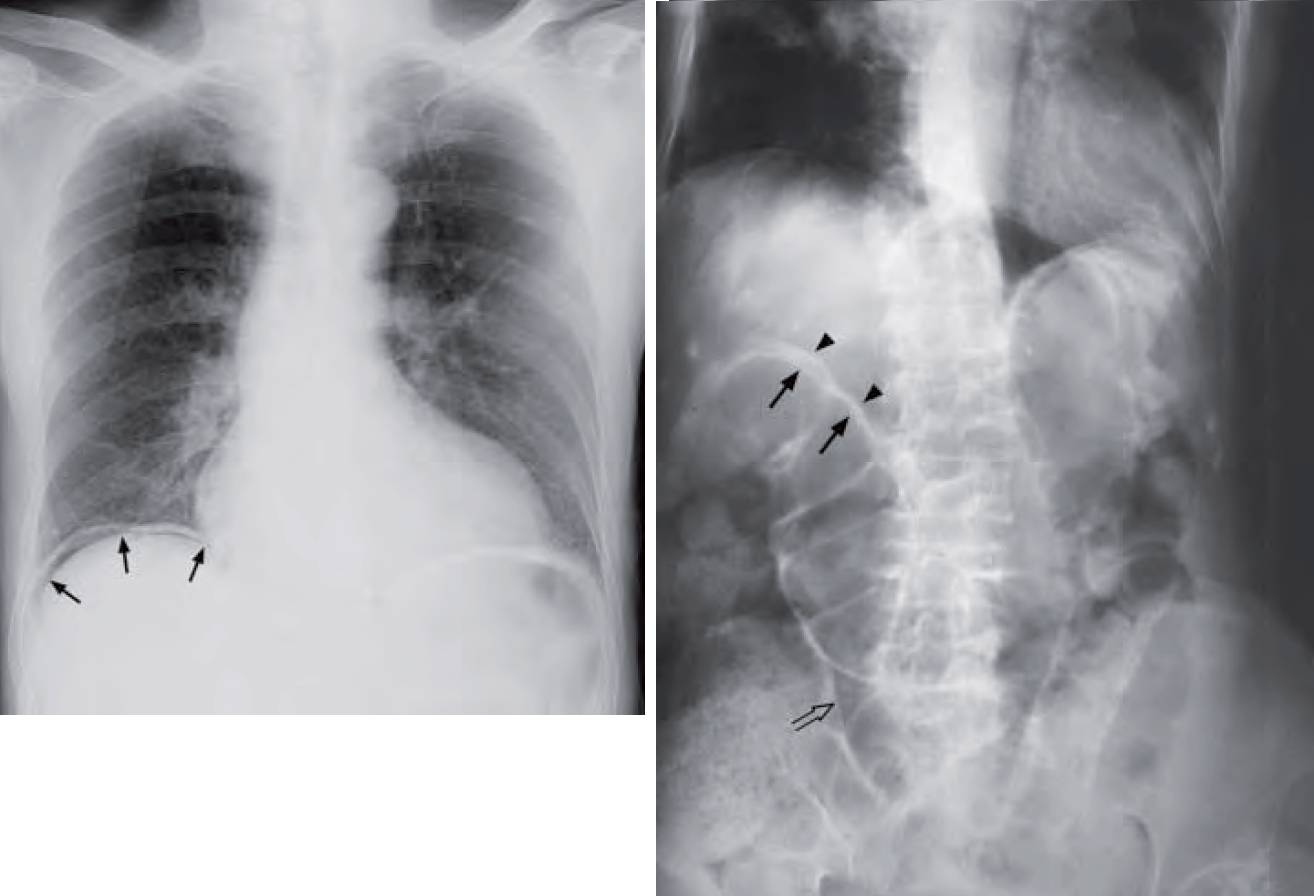

- Right Image: Supine abdominal radiograph showing signs of extraluminal gas including the Rigler’s sign (also known as double wall sign) and triangular sign.

Right Image: Rigler’s sign (also known as the double wall sign) – the inner mucosal surface of the bowel wall is delineated by intraluminal air (arrows) and the outer serosal surface of the bowel wall is also delineated by extraluminal intraperitoneal free air (arrow heads). Note the triangular collection of gas between adjacent loops of bowel (open arrow) – triangular sign.

- Rigler’s sign – bowel wall outlined by intraluminal (normal) and peritoneal gas (abnormal)

- Triangular sign – gas collecting between adjacent bowel loops